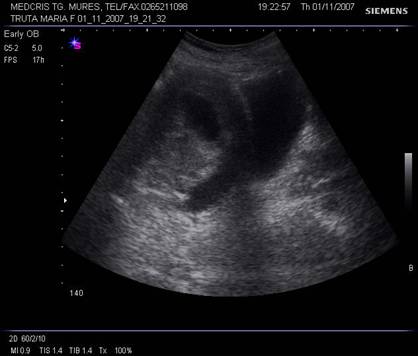

Fig. nr.346. Sectiune sagitala prin pelvis la ecografia abdominala, uter premenarcha

Fig. nr .348.Uter postmenarcha ,la ecografia abdominala , sectiunea sagitala